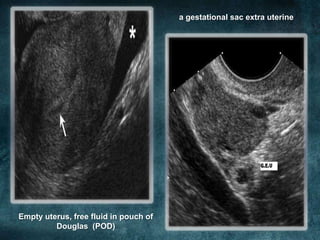

COMMENT THE

ULTRASOUND

FINDINGS?

a gestational sac extra uterine

Empty uterus, free fluid in pouch of

Douglas (POD)

RUPTURED

ECTOPIC

PREGNANCY

• An emergency laparatomy was done and

found to have 2 litres of haemoperitonium

and ectopic pregnancy of right tube.

• Subsequently, right salphingectomy was

done and she was discharged after 3 days

from ward.